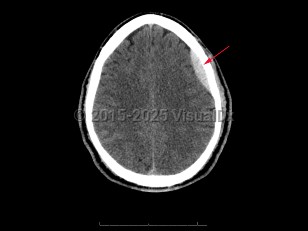

PapilledemaPapilledema